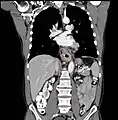

Esophageal cancer as shown by a filling defect during an upper GI series

Although an occlusive tumor may be suspected on a barium swallow or barium meal, the diagnosis is best made with an examination using an endoscope. This involves the passing of a flexible tube with a light and camera down the esophagus and examining the wall, and is called an esophagogastroduodenoscopy. Biopsies taken of suspicious lesions are then examined histologically for signs of malignancy.

Additional testing is needed to assess how much the cancer has spread (see #Staging, below). Computed tomography (CT) of the chest, abdomen and pelvis can evaluate whether the cancer has spread to adjacent tissues or distant organs (especially liver and lymph nodes). The sensitivity of a CT scan is limited by its ability to detect masses (e.g. enlarged lymph nodes or involved organs) generally larger than 1 cm.[41][42] Positron emission tomography is also used to estimate the extent of the disease and is regarded as more precise than CT alone.[43] Esophageal endoscopic ultrasound can provide staging information regarding the level of tumor invasion, and possible spread to regional lymph nodes.